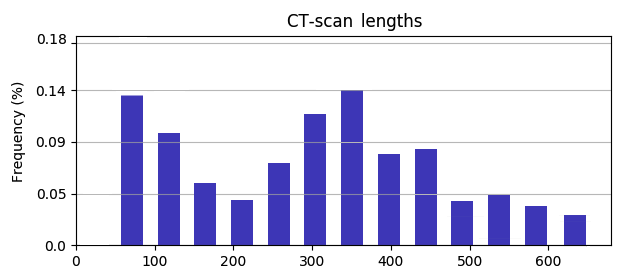

Annotation of each CT slice has been performed by 4 very experienced (each with over 20 years of experience) medical experts; two radiologists and two pulmonologists. Labels provided by the 4 experts showed a high degree of agreement (around 98%). Each of the 3-D scans includes different number of slices, ranging from 50 to 700. This variation in number of slices is due to context of CT scanning. The context is defined in terms of various factors, such as the accuracy asked by the doctor who ordered the scan, the characteristics of the CT scanner that is used, or specific subject’s features, e.g., weight and age.

Such approaches require large training datasets. A few databases with CT scans have been recently developed [10], [11]. However, a rather fragmented approach is followed: research is based on specific datasets, provided by small, or larger numbers of hospitals, with no proof of good performance generalization over different datasets and clinical environments. Moreover, many datasets are small, in terms of total CT scans, or scan slices, or COVID-19 annotated CT scans, or number of patients [12]. In this paper we use a new very large database, COV19-CT-DB, which we have developed, including chest 3-D CT scans, aggregated from different hospitals. In particular, it includes 7,750 3-D CT scans, annotated for COVID-19 infection; 1,650 are COVID-19 cases and 6,100 are non-COVID-19 cases. The 3-D CT scans consist of different numbers of CT slices, ranging from 50 to 700, totalling around 2,500,000 CT slices. Part of the database was successfully used in a recently held Competition [13]. The whole database is being currently made available to the research community through our website.